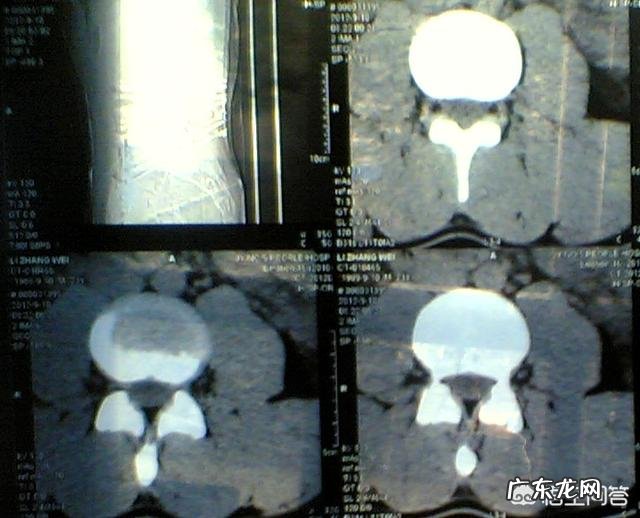

腰椎间盘膨出,从退变来讲,属于椎间盘突出中最轻微的一种,只是纤维环变形膨隆,纤维环也没有破裂,属于较轻的一类,也没有医生会推荐膨出的患者做微创或手术处理 。

不过膨出未必一定症状轻,突出未必症状一定重,我遇到过不少的患者,腰椎盘膨出急性期的时候,腰痛的很剧烈,走路都支撑不住上半身,夜间也不能翻身,膨出腿痛的相对较少,腰痛居多 。